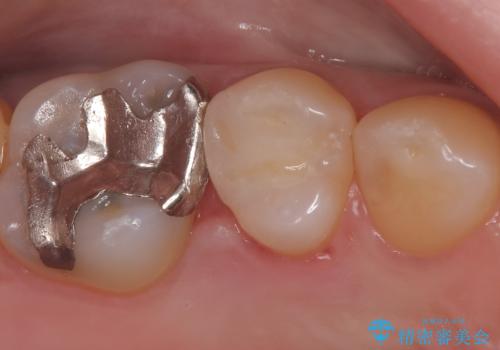

セラミックインレー 虫歯の治療

- 定期健診で虫歯が見つかり、治療が必要となりました。材料の物性を説明し、セラミックインレーでの治療となりました。

接着操作時にはラバーダム防湿を行いました。